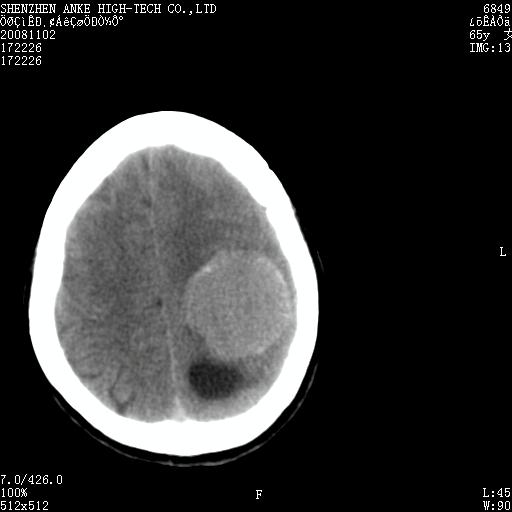

患者,女性,65岁,突发右侧肢体无力伴头痛,恶心、呕吐3小时.

1 左侧顶区圆形病灶,内可见钙化,考虑脑膜瘤,建议增强。2 左侧侧脑室病变,考虑神经上皮囊肿。

1)左侧顶区脑膜瘤可能性大;建议必要时行进一步检查。2)左侧脑室积水。

左顶部脑膜瘤,左侧侧脑室蛛网膜囊肿,建议增强.

左侧脑外占位(脑膜瘤)压迫脑实质、脑室侧室孔所致积水。支持!